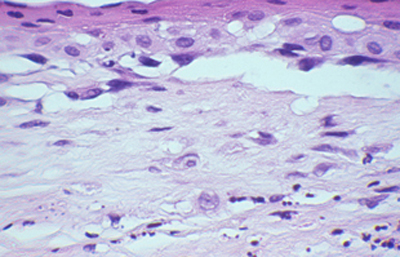

Cuando el examen patológico se realiza en cortes de tejido corneal procesados en parafina, (biopsias y discos de córnea de queratoplastias) las coloraciones que empleamos usualmente son la coloración de Hematoxilina-Eosina (Figura 49), el Blanco de Calcofluor. (Figura 50), la de PAS (Figura 51 y 52). De nuevo, la consideración de que una infección corneal puede ser causada por Acantamoebas es la condición indispensable en el diagnóstico diferencial para llegar a su diagnóstico

Fig. 49 H-E, Original x160

Fig. 51 PAS, Original x160

Fig. 52 PAS, Original x160